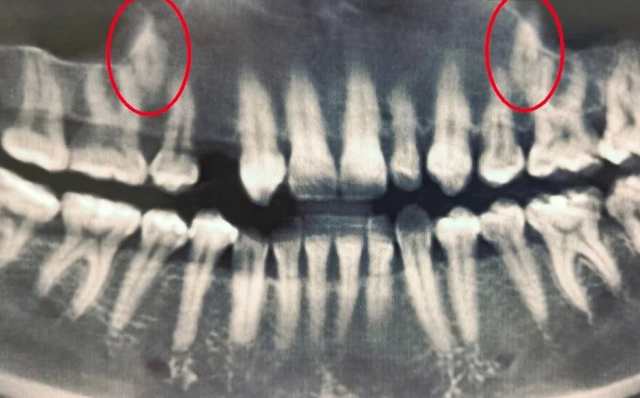

Женщина обратилась в областную стоматологическую поликлинику ещё в 2023 году. Врачи провели тщательное обследование с компьютерной томографией: оно позволило детально оценить положение непрорезавшихся зубов относительно других элементов зубочелюстной системы. У женщины в ряду не было одного зуба, а другой был намного меньше нормы. Из-за этого врачи решили «переместить» их в ряд. Пациентке установили брекеты и 1,5 года создавали место для этих зубов. После хирургического раскрытия коронок ретенированных зубов стоматологи зафиксировали ортодонтические кнопки для вытяжения. С помощью дополнительных рычагов и пружин один из зубов уже вышел из костной ткани, а второй проходит кортикальную пластинку, то есть – прорезается.